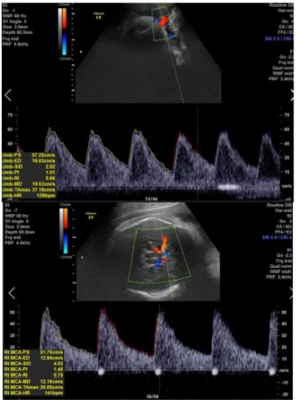

Primigesta, 42 anos, idade gestacional de 36 semanas e 1 dia, sem comorbidades prévias, assintomática, exame clínico sem alterações. Realizou ultrassonografia obstétrica com dopplerfluxometria por queda no crescimento da altura uterina nas últimas semanas. Feto único, vivo, apresentação cefálica, sem mal formações visíveis, peso estimado fetal de 2.100g, percentil 3, índice de líquido amniótico = 2,7cm; movimento respiratório presente, doppler demonstrado abaixo: Valores referência para idade gestacional: Umbilical PI: 0,69 a 1,09 – Umbilical A/B: 1,40 a 3,75 ACM PI: 1,42 a 2,04 ; Quando devemos considerar a realização do parto?